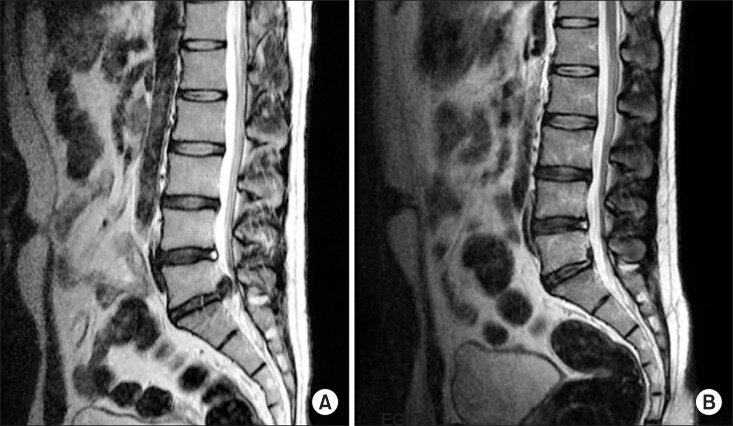

Сагиттальные снимки МРТ другого пациента с ЛДГ до (А) и после лечения (Б). Через 16 месяцев после лечения у пациента не было симптомов

Клиническое улучшение может происходить либо без каких-либо заметных морфологических изменений, либо симптоматическое выздоровление может предшествовать уменьшение грыжи на МРТ. Этот результат можно объяснить постепенным уменьшением давления, оказываемого грыжей межпозвоночного диска на соседние нервные структуры, и снятием воспалительного синдрома.